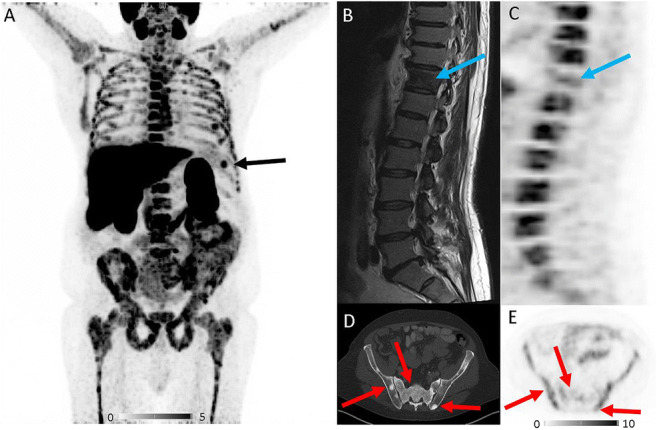

A patient with Gleason 6 prostate carcinoma (initial diagnosis April 2012) underwent [18F]PSMA 1007 PET/CT for restaging. After several years of watch and wait, bone metastases were detected in November 2017 with bone scintigraphy (oligometastatic disease), and anti-androgenic therapy was initiated. PSA values initially dropped, then after significant PSA relapse in March 2019 (PSA value 153 ng/ml), a second-line antihormonal therapy with abiraterone was started. Restaging with bone scintigraphy and MRI in June 2020 revealed contradictory findings. Whereas MRI findings suggested multifocal disease, the bone scan still indicated oligometastatic bone disease. For clarification, [18F]PSMA 1007 PET/CT was performed. PSA value at the time of imaging was 0.2 ng/ml. Additionally, the patient has been suffering from polycythemia vera (PV) for about 20 years, which is currently under therapy with hydroxyurea since December 2019. Splenectomy has been performed already in September 2019. [18F]PSMA 1007 PET/CT showed intense tracer uptake in the bone marrow compartment of the entire skeleton with few focal spots (A). A small accessory spleen also showed an intensive tracer uptake (A, black arrow). T1-weighted MRI of the vertebral column revealed a signal loss in vertebral bodies to the level of spinal discs, indicating a replacement of fatty bone marrow by the red bone marrow (B). Metastatic thoracic vertebra 11 presents without tracer uptake (B, C, blue arrows). Furthermore, CT revealed multiple osteoblastic lesions in the entire skeleton but without relevant tracer uptake (D, E, red arrows), indicating disease control or non-viable bone metastases under current antihormonal therapy with abiraterone, as shown recently by Plouznikoff et al. for patients receiving novel antiandrogen drugs [1]. In conclusion, increased [18F]PSMA 1007 uptake in the bone marrow compartment is most likely caused by PV, rather than bone metastases from prostate cancer.